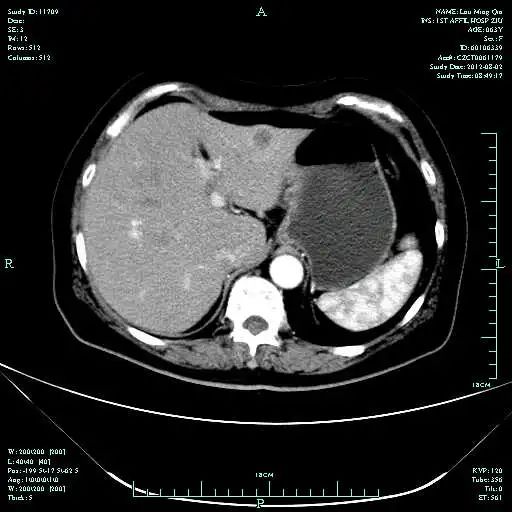

CT-T

CT-H1

MR-H1

影像学检查结果评估:cPD。

• 第三次FOLFOX+T方案后 B超提示肝转移灶消失